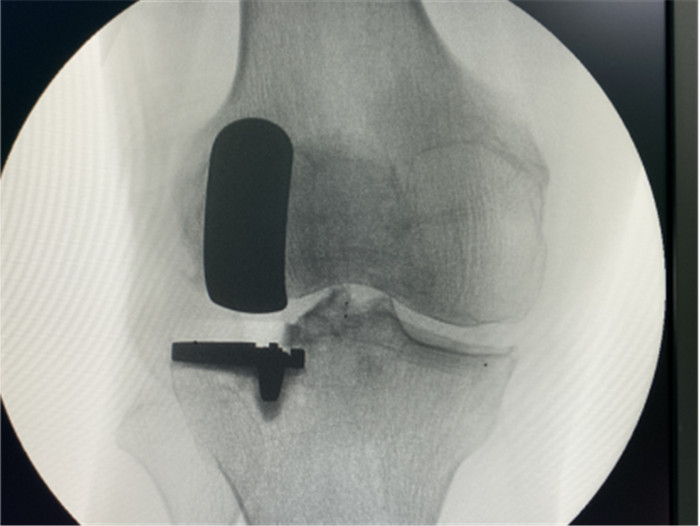

一個(gè)單髁置換手術(shù)要想達(dá)到理想的手術(shù)治療效果并不簡(jiǎn)單,這與假體的大小、方向和松緊度密切相關(guān),其中任何一點(diǎn)出現(xiàn)差池,結(jié)果都會(huì)差強(qiáng)人意。為此,羅主任團(tuán)隊(duì)在術(shù)前和術(shù)中進(jìn)行了精確的設(shè)計(jì)和測(cè)量,制定周密手術(shù)方案,順利為病人實(shí)施手術(shù),幫助膝關(guān)節(jié)“補(bǔ)牙”。

單間室局部修補(bǔ)